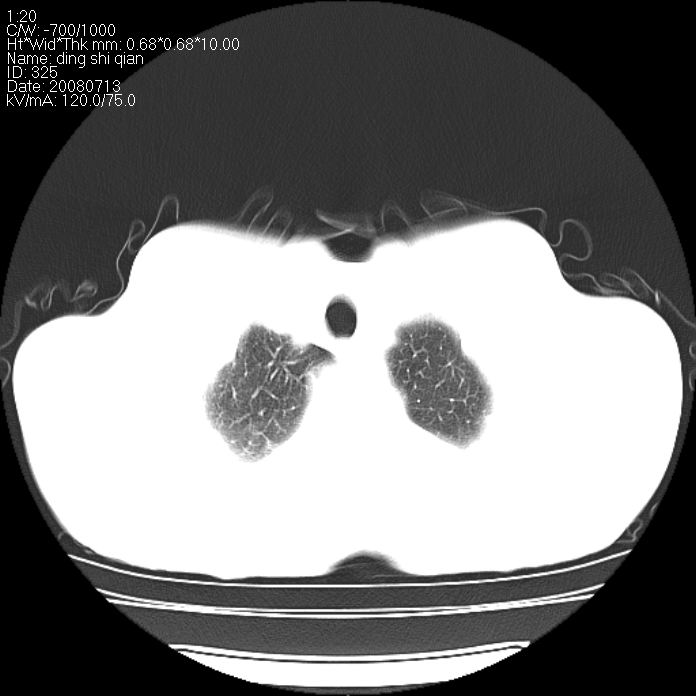

标题: CT14654:男 50岁 近来胸痛 [打印本页]

标题: CT14654:男 50岁 近来胸痛

右侧上肺块状软组织影,浅分叶,边缘毛刺证,与胸膜粘连,考虑:周围性肺癌

右侧上肺块状软组织影,浅分叶,边缘毛刺证,与胸膜粘连,考虑:周围性肺癌!支持!